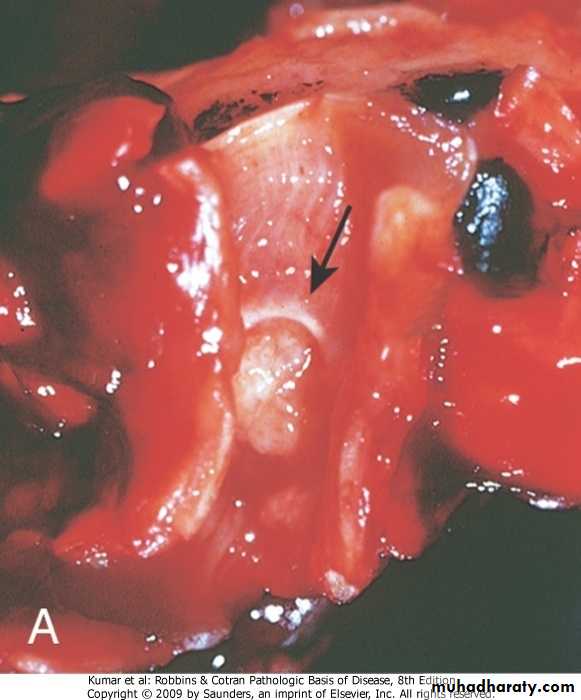

Bronchiectasis

Abnormal and permanent dilatation of the bronchi .It is common and affects all age groups characterized by cough with large amount of foul odor sputum. Hemoptysis

Bronchiectasis :Pathology

Gross:It may affects any part of the lung but the basal segments are commonly involvedThe dilatation may be Cylindrical (involve all the circumference ) or Sacular (involve part of the circumferences),

Bronchogram demonstrate the dilatation nicely

Grossly: Bronchiectasis